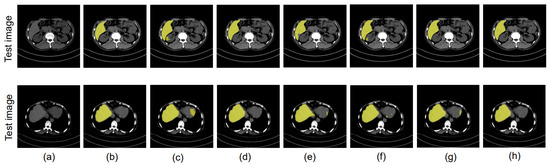

4.8. Ablation Study

4.8.1. Different Datacenter and Same Phase

4.8.2. Same Datacenter and Different Phase

4.8.3. Different Datacenter and Different Phase